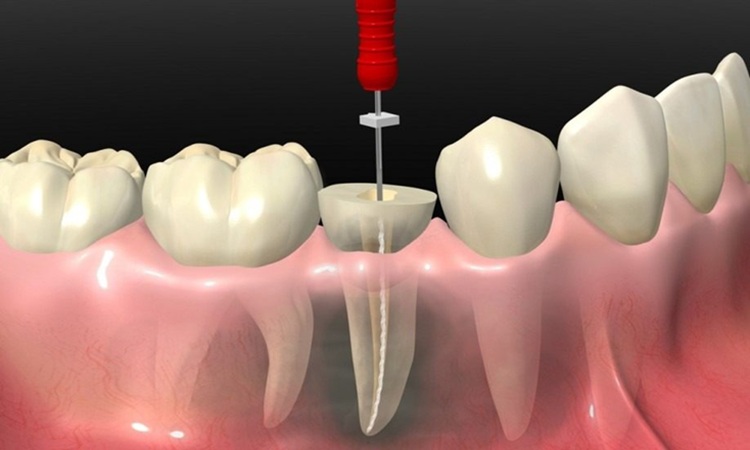

ترمیم بعد از عصب کشی: چرا ضروری است؟

بعد از عصب کشی، دندان تا حد زیادی ضعیف و شکننده می شود و بدون محافظت مستعد شکستن یا ترک خوردن است. بنابراین ترمیم بعد از عصب کشی ضروری است تا ساختار دندان حفظ شود، از نفوذ باکتری ها جلوگیری شود و عملکرد جویدن به حالت طبیعی بازگردد. این ترمیم می تواند موقت یا دائمی باشد، بسته به نیاز و برنامه درمانی دندانپزشک.

ترمیم موقت چیست و چه کاربردی دارد؟

ترمیم موقت یک پوشش کوتاه مدت است که پس از عصب کشی روی دندان قرار می گیرد تا آن را از باکتری ها، فشار جویدن و آسیب های احتمالی محافظت کند. این نوع ترمیم معمولاً تا زمان آماده شدن تاج دائمی یا درمان نهایی دندان استفاده می شود و به دندان اجازه می دهد بدون درد یا عفونت باقی بماند. ترمیم موقت سریع نصب می شود و معمولاً از مواد کمتر مقاوم ساخته شده است، بنابراین برای استفاده طولانی مدت مناسب نیست.